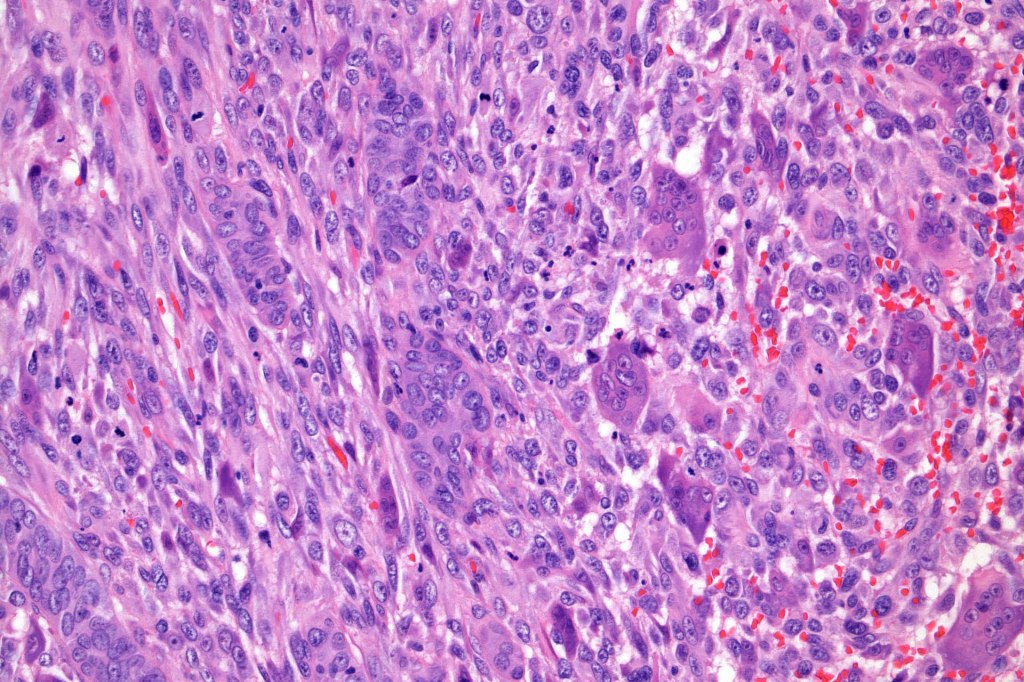

•The epithelial component is composed of uniform small, basophilic devoid of desmosomes

•Peripheral palisading

•Retraction artifact with stromal mucin

•Mitoses often very marked

•Apoptosis